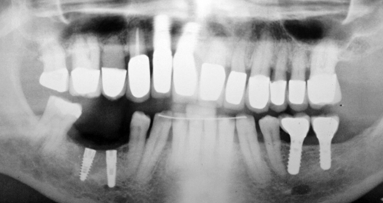

In the present case report, a new method that allows impression taking of implants inserted at a steep angle is presented. The use of implants for the ...